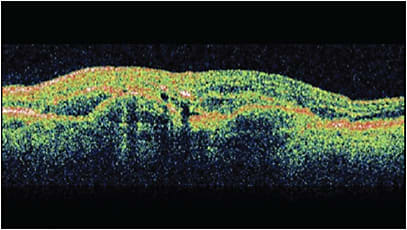

Subretinal and Intraretinal Fluid

When either subretinal fluid (SRF) or intraretinal fluid (IRF) is the overriding anatomic change on OCT (Figure 2), the goal historically and practically has been complete anatomical resolution with titration of dosing intervals toward that endpoint.19 Importantly, the anatomic location of the fluid prognostically may be important, because retrospective analysis of CATT data implies that small amounts of subretinal fluid may be compatible with good visual outcomes, but intraretinal fluid has poor prognostic implications and a higher association with development of atrophy and subretinal fibrosis.4,20,21

However complete resolution of fluid is not always achievable. New evidence may even suggest that patients with a small amount of stable SRF may sometimes have better vision than their dry counterparts.21 This may be from atrophy, which is associated with increasing numbers of injections,22 or from some reason not yet understood. The FLUID study examined treat-and-extend with ranibizumab while allowing up to 200 µm of subfoveal fluid. The authors found comparable visual outcomes with lengthened intervals and a modest reduction in the total number of injections over 2 years compared with using tighter anatomic endpoints.23 Further study over longer durations and with other agents may elucidate the pathophysiology and optimize the approach to residual fluid.